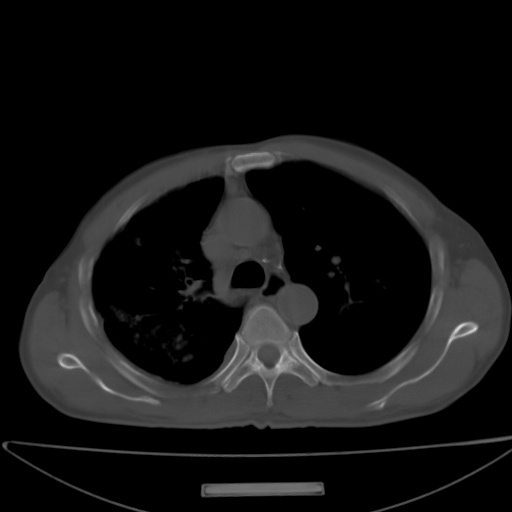

以下是引用jsgdoctor在2008-11-6 22:12:00的发言:[br]右主支气管壁明显增厚,管腔狭窄.考虑为右侧中央型肺癌伴阻塞性炎症\\肺脓肿.

以下是引用zjzjr在2008-11-6 20:25:00的发言:[br]中心型肺ca,合并阻塞性肺炎

以下是引用zsl6918在2008-11-6 19:43:00的发言:[br]右侧中心性肺癌(鳞癌)